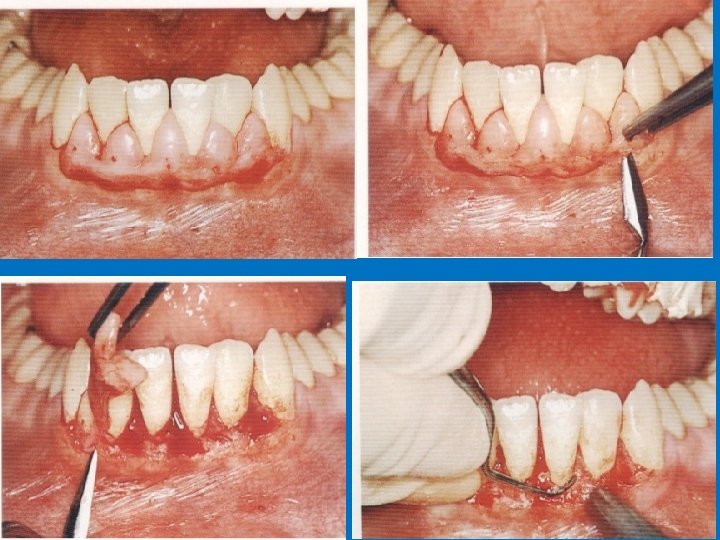

Internal bevel incision: Is basic to most periodontal flap procedures. 1 - It removes the pocket lining. 2 - conserves the outer surface of gingiva. 3 - It produces a sharp, thin flap margin for adaptation to the bone tooth junction.

Vertical Incision :

Modified Widman flap

. : 3. Flap retraction

Root planing with direct vision… THE MOST IMPORTANT STEP IN SURGICAL PROCEDURE 5 -Direct root planning